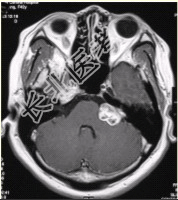

- [材料题] 患者女,40岁。左侧听力下降半年,临床治疗效果不显著。MRI增强检查如下图。

- 简答题1、请问该患者可能的诊断是什么?

- 简答题2、请问该病常见症状有哪些?

- 简答题3、请问该病治疗方法通常包括哪些?